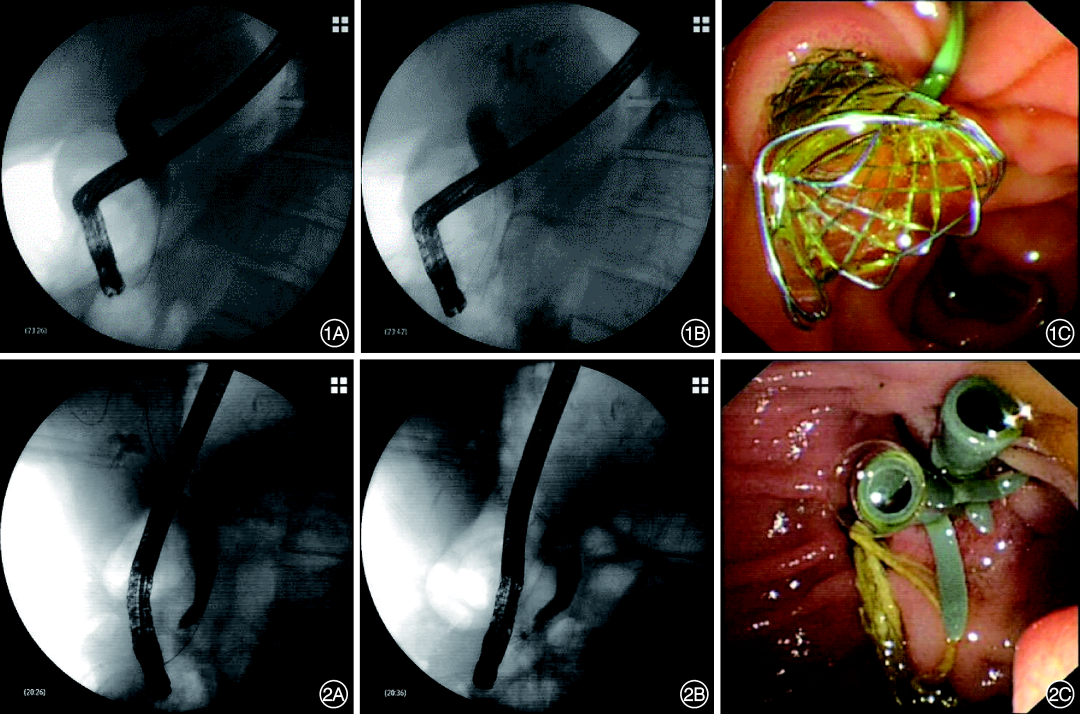

2.内镜操作:患者术前均签署知情同意书。经验丰富且具有高级职称的内镜医师经十二指肠乳头选择性胆管插管,并进行胆管造影,必要时进行胆胰管共同造影。根据患者病情,选择性行乳头扩张、狭窄段扩张、气囊/网篮取石操作。评估患者胆管狭窄的位置及长度后,根据内镜医师个人经验置入1根FCSEMS(图1)或2~3根塑料支架(图2),根据胆管狭窄程度决定支架数量。置入多根塑料支架时先插管在胆管狭窄段置入第1根塑料支架,而后退出导丝,再重新进导丝置入后续支架,支架与支架之间并列。对于插管困难或导丝反复进入胰管的患者常规行十二指肠乳头切开术和胰管支架置入术。胆管和胰管支架置入后,注入造影剂观察引流是否通畅。

1 全覆膜金属支架治疗良性胆管狭窄 1A:经内镜逆行胰胆管造影提示胆总管下段狭窄;1B:置入全覆膜自膨式金属支架后造影,可见支架在位;1C:内镜下见支架末端位于乳头外

2 多根塑料支架治疗良性胆管狭窄 2A:经内镜逆行胰胆管造影提示胆总管下段狭窄;2B:置入2根圣诞树塑料支架后造影,可见支架在位;2C:内镜下见圣诞树支架外口位于乳头外